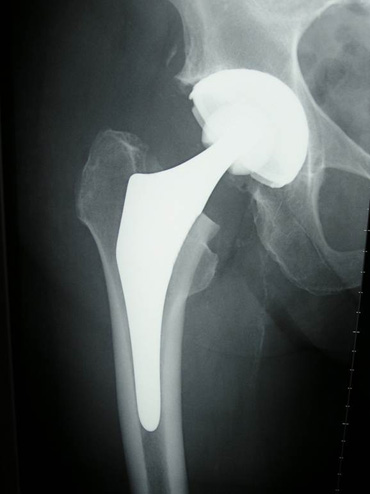

- Implantation von Totalendoprothesen an Hüft-, Knie und Schultergelenk inkl. Wechseloperationen